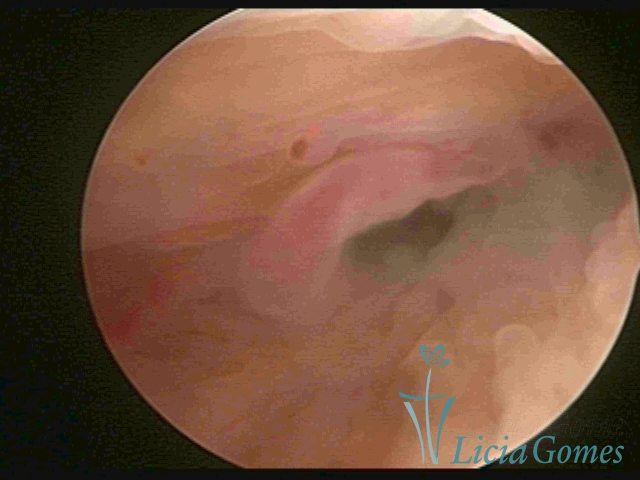

ENDOCERVICAL POLYPS

Benign tumors resulting from the reactive focal proliferation to inflammatory processes or hyperestrogenism situations, which may be sessile (with a large implantation) or stalked.